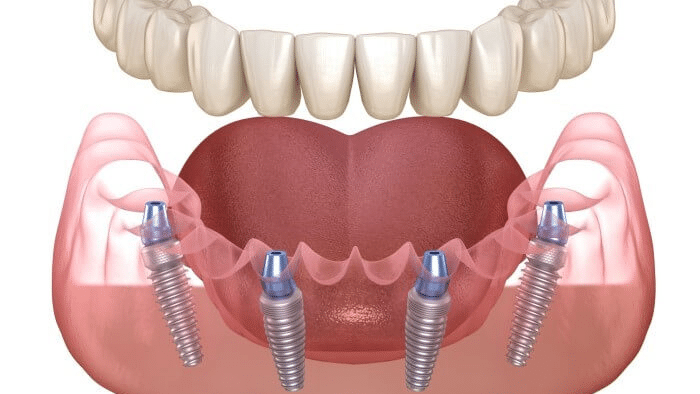

インプラントは、

- 先程説明した顎骨に埋め込む下部構造(インプラント体)

- 目視で確認できる上部構造(被せ物)

の2つからできていますが、この上部構造(被せ物)の材質によっても治療費が異なります。

▼インプラントの上部構造の種類

| 材質 | 費用 | 特徴 |

|---|---|---|

| ハイブリッドセラミック | 中 | 費用は比較的安いが、耐久性があまりなく変色しやすい |

| オールセラミック | 高 | 審美性に優れているが、ジルコニアに比べて耐久性が低い |

| ジルコニア | 高 | 審美性が高くセラミックに比べて耐久性も高いが、過度な歯ぎしりがある方は対策しないと歯がすり減る可能性がある |

当院のオールオン4の上部構造(被せ物)は、耐久性が高いジルコニアを採用しております。

なぜなら、オールオン4は寿命が長く、しっかりメンテンスをすれば半永久的に使える人工歯だからです。

単純な初期コストの安さよりも、長期視点でコスパが良い材料を優先して選んでおります。

オールオン4は、たった4本のインプラントで片顎すべての歯を支えます。

また、顎に埋め込むインプラントの

- 位置

- 角度

- 深さ

などによって、バランスが大きく変化する非常に難易度の高い治療法なのです。